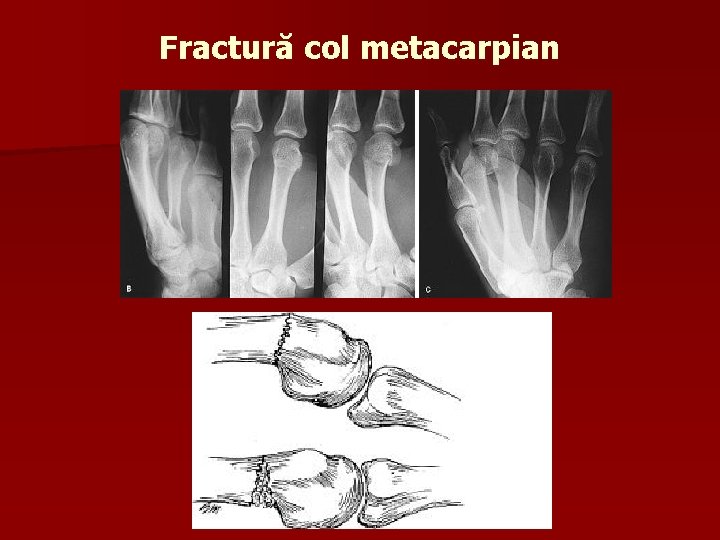

Fractură col metacarpian